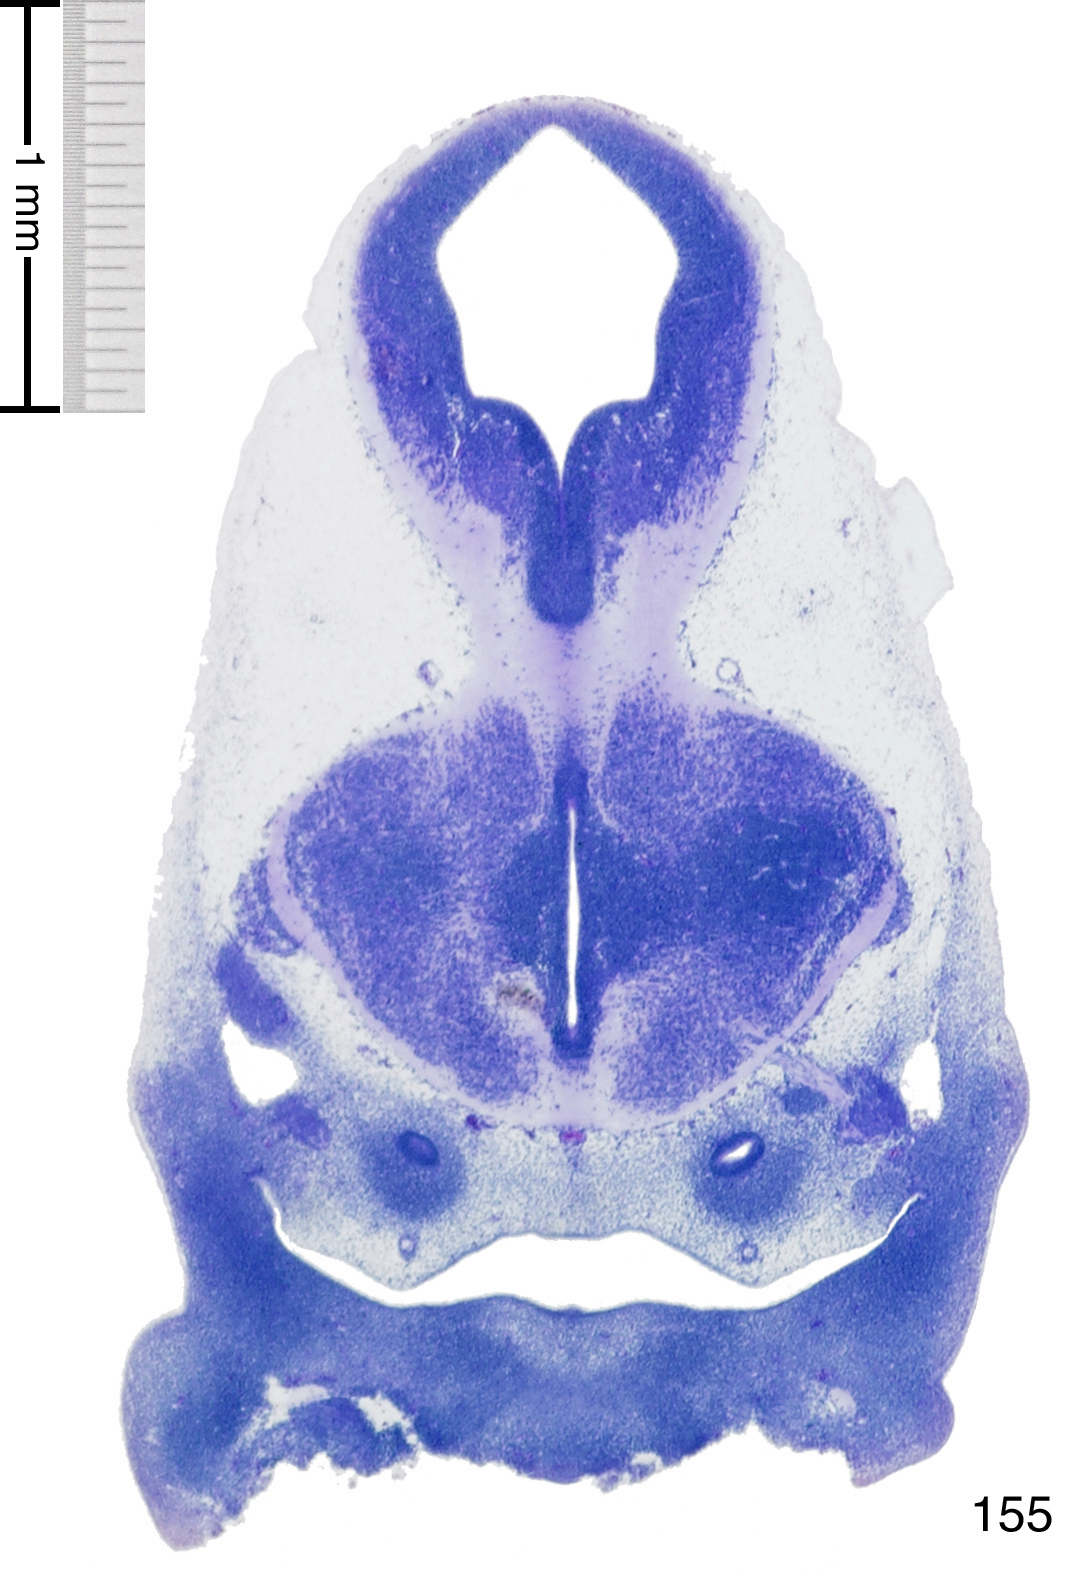

C57BL/6J GD12 Mouse Brain Atlas

Slides from U. Schambra, coronal cuts with slides at every 5th section, with a hematoxylin and eosin (H & E) stain

Currently on section 155.